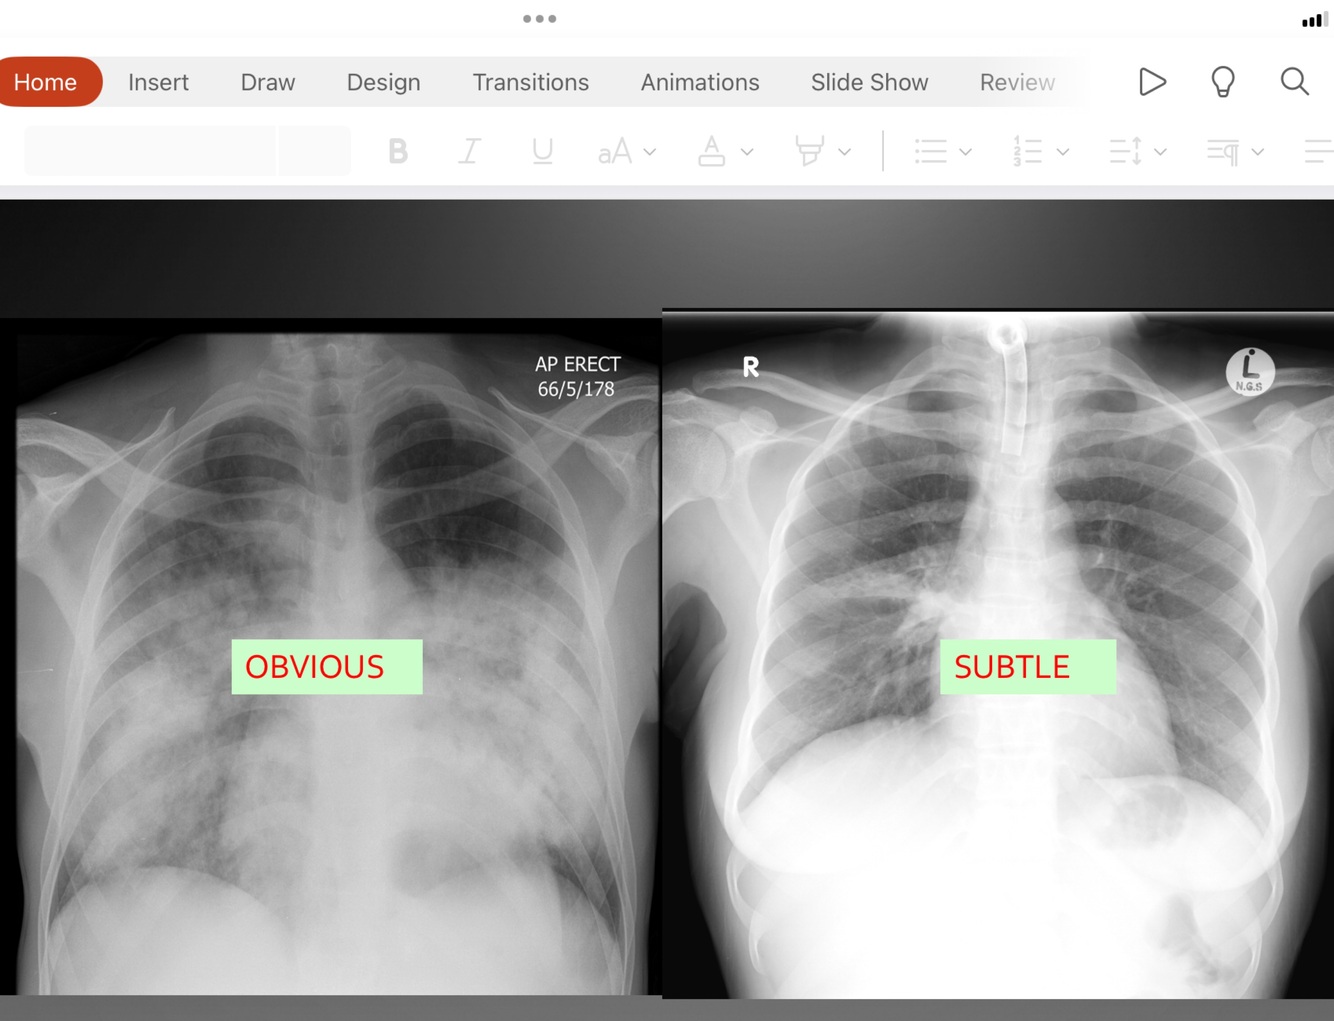

Which sign on xray

Consolidation

Consolidation signs on CXR

-air bronchogram sign= increased density. Tubular air filled bronchi made obvious

-silhouette sign= loose silhouette because density between lung and other tissues are not as easily visible. Cant see boarders very well.